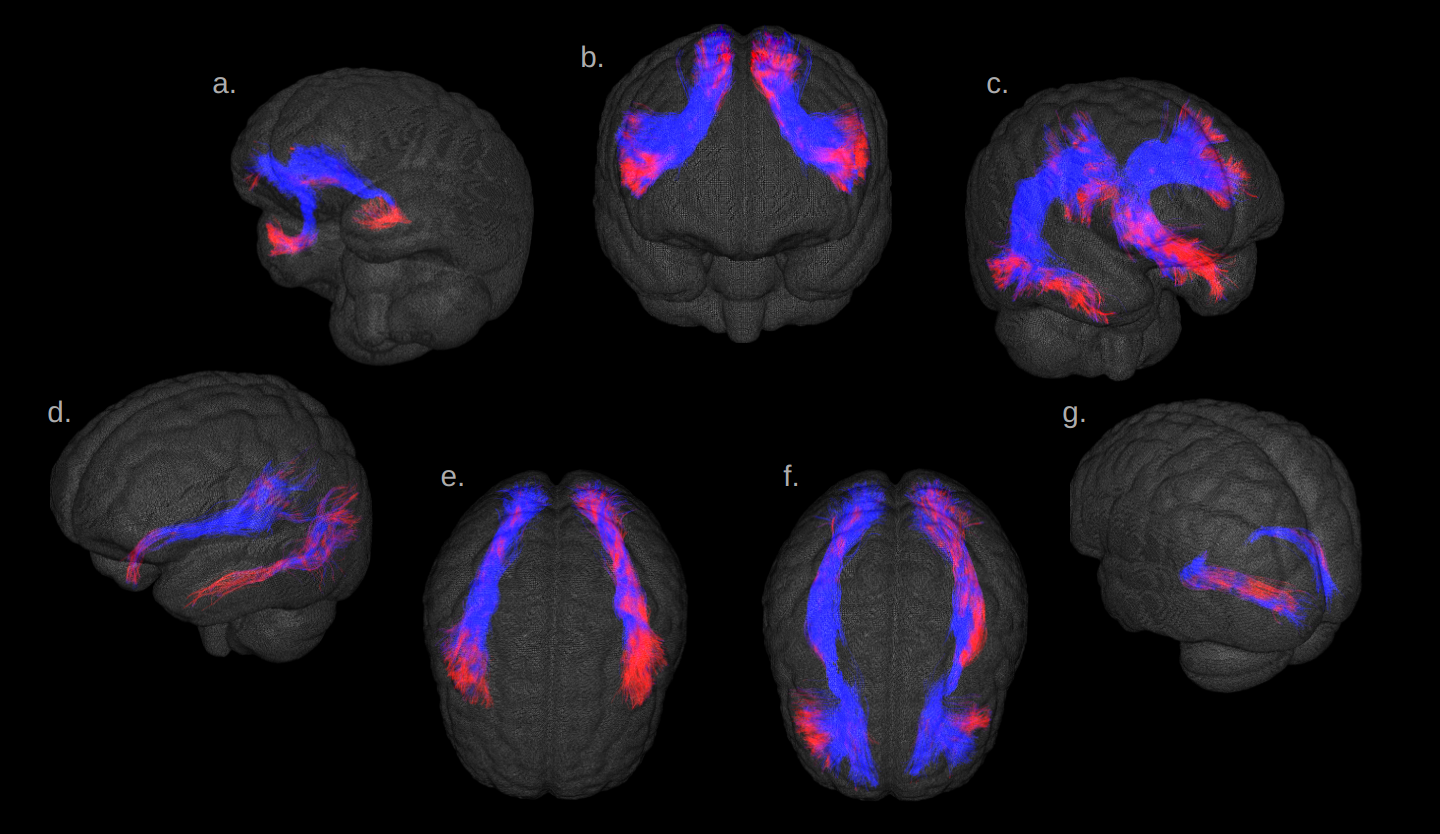

Fig.1 illustrates the preparation and post-processing pipeline from the gelatin injection step till the projection of MCA volume contribution for each deep WM bundle. Fig.2 depicts axial and coronal slices of the MCA volume fraction map overlaid onto the corresponding proton density map computed from the T2-weighted qMRI data. Fig.3 shows the statistical analysis highlighting the MCA contribution in the vascularization of deep WM bundles. Fig.4 illustrates the vascularization of the most MCA-irrigated deep WM bundles (arcuate, frontal aslants, inferior fronto-occipital, inferior/middle longitudinal, optic radiations, uncinate and ventral visual stream).

Figure 4: MCA volume fraction projected (in red) on the main MCA-irrigated bundles, (a) uncinate, (b) frontal aslants, (c) arcuate, (d) ventral visual stream, (e) inferior and middle longitudinal, (f) inferior fronto-occipital fasciculus (IFOF), (g) optic radiations.